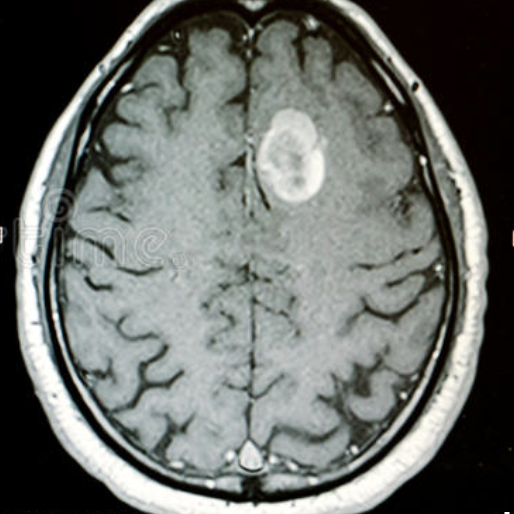

BALANCE is dedicated to building research infrastructure and capacity in collaboration with local and international partners to advance global neurology and health equity research that improves quality of and access to neurological care.